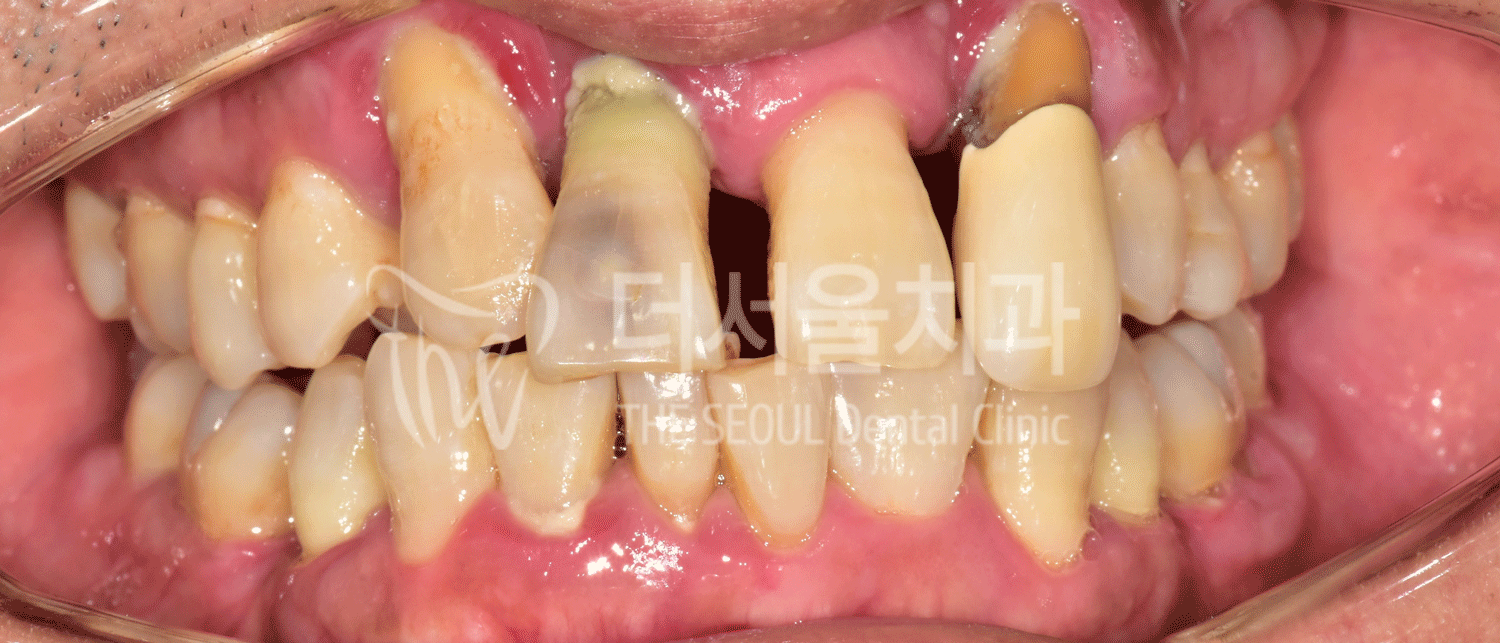

다시 본론으로 돌아가 초진 사진을 보면

전치부 치아들의 상황이 좋지 않아

금방이라도 빠질 거 같은 모습이었습니다.

이렇게 눈에 잘 띄는 곳은

제때 진료를 받지 않으면,

심미적인 문제는 물론이며

추후 심리적인 측면에도

좋지 않은 영향을 끼치게 됩니다.